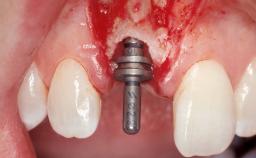

Immediate Flapless Placement of an Implant in a Maxillary Left Central Incisor Site

A 42-year-old female patient was referred to our clinic at the School of Dentistry of the University of São Paulo in November 2004, presenting a deficient restoration in the upper left central incisor. The clinical examination revealed no gingival retraction or any signs of gingival inflammation and, therefore, previous periodontal treatment was not considered. The patient presented a high lip line at full smile and a thin tissue biotype. This combination characterized a high-risk situation from an anatomic point of view, which required careful preoperative planning and cautious surgical execution.

Placement Protocol Immediate implant placement

Tooth Site Maxillary incisor or canine

Socket Morphology Single-root socket

Socket Integrity Sufficient, with intact bone walls